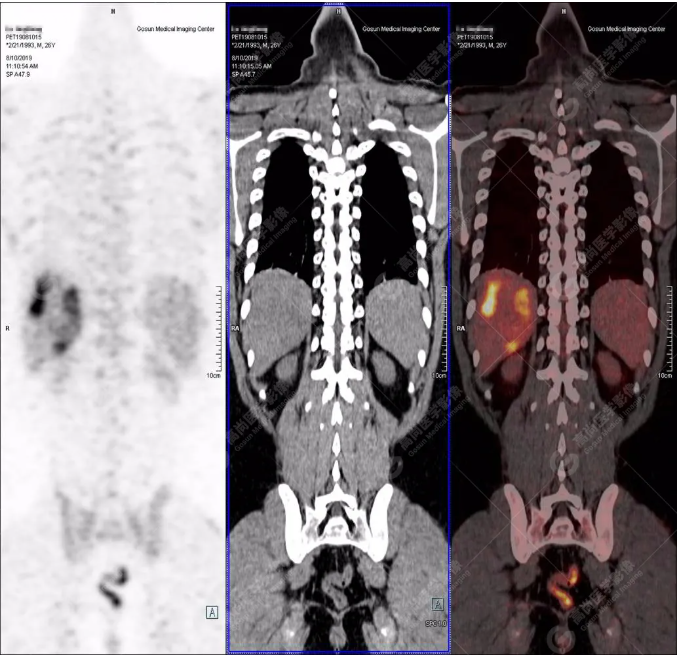

PET/CT全身圖

PET/CT診斷

嗜酸性粒細(xì)胞增多癥肝浸潤

隨訪

根據(jù)骨髓穿刺及抗寄生蟲治療后好轉(zhuǎn)情況,最終確診為嗜酸性粒細(xì)胞增多癥肝浸潤(肝寄生蟲病所致)